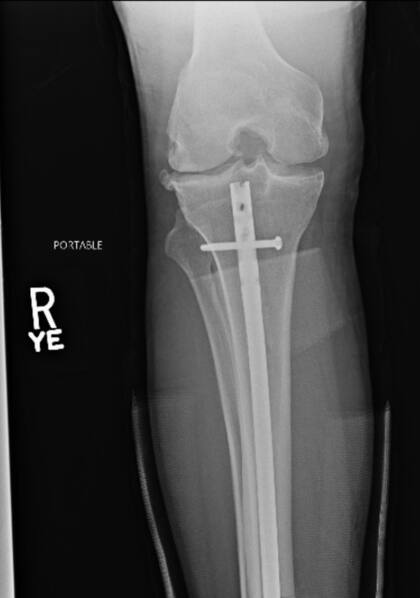

El sábado pasado, Chris Weidman se rompió la pierna en pleno combate contra Uriah Hall. Cuando apenas habían pasado 17 segundos del primer round entre los luchadores de UFC, el neoyorquino de 36 años le lanzó una patada al jamaiquino de su misma edad y terminó tumbado en el piso con una fractura de tibia y peroné. Ahora, el peleador de artes marciales mixtas mostró cómo quedó tras pasar por el quirófano.

“Algunas radiografías antes y después de la operación”, escribió en Twitter, junto a un par de imágenes donde mostraba cómo tenía la pierna apenas fue hospitalizado y cómo le quedó tras la cirugía, donde le colocaron una serie de clavos.

En una entrevista con el medio norteamericano TMZ, Weidman contó que le pusieron una varilla de titanio a través de la tibia y dijo que también se le había roto el peroné. Tal lesión lo obligará a estar entre seis y 12 meses en reposo para poder volver a los entrenamientos.